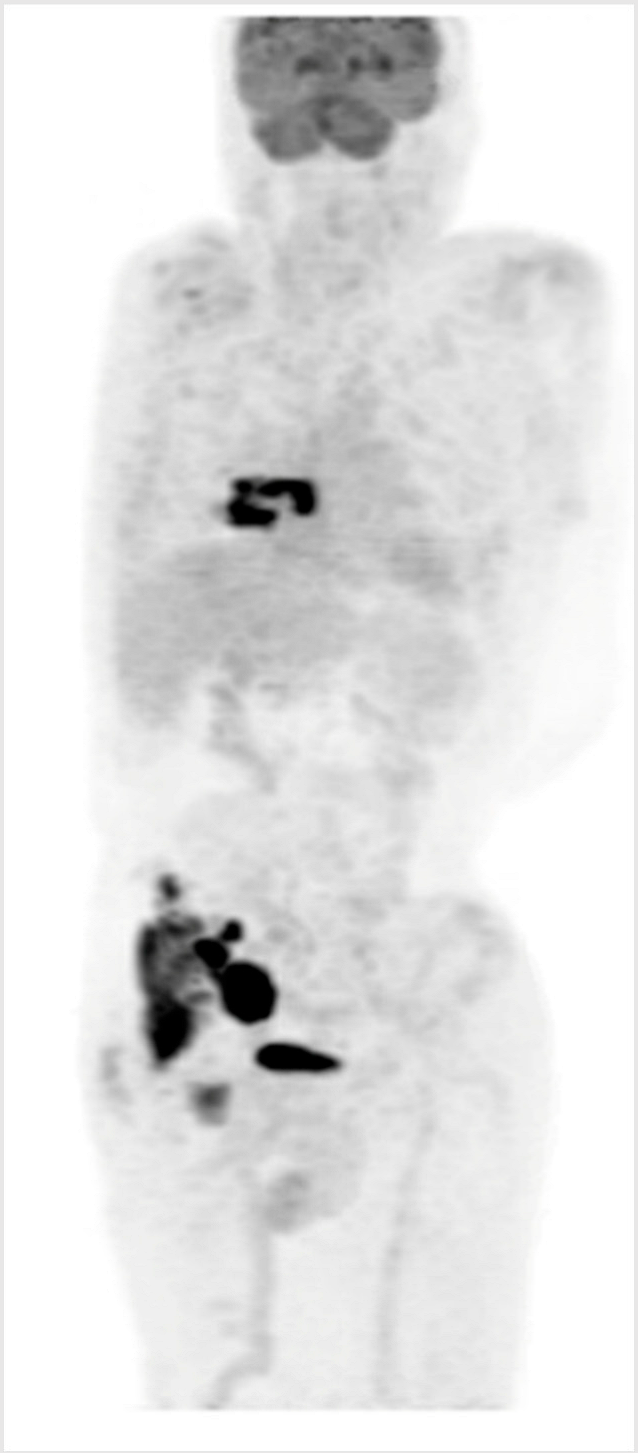

3.4. Illustrative Case 4

Key clinical features

| ![]() |

ASCT—autologous stem cell transplant; BsAB—bispecific antibody; CT—computerized tomography; CR—complete response; DLBCL—diffuse large B-cell lymphoma; ECOG—Eastern Cooperative Oncology Group; LDH—lactate dehydrogenase; PET—positron emission tomography; PS—performance status; R-CHOP—rituximab–cyclophosphamide–doxorubicin–vincristine–prednisone; R-GDP—rituximab–gemcitabine–dexamethasone; ULN, upper limit of normal.

Key Points for Illustrative Case 4

- Unfortunately, this otherwise healthy man exhibits chemo-refractory disease after an initial benefit from R-CHOP and did not sustain a durable benefit from CAR-T cell therapy;

- BsAbs have demonstrated efficacy for patients with R/R DLBCL regardless of prior exposure to CAR-T cell therapy [1,3]. This case illustrates the potential use of BsAbs following CAR-T cell therapy failure, with CAR-T cell therapy initially prioritized due to its longer available follow-up and known curative potential.